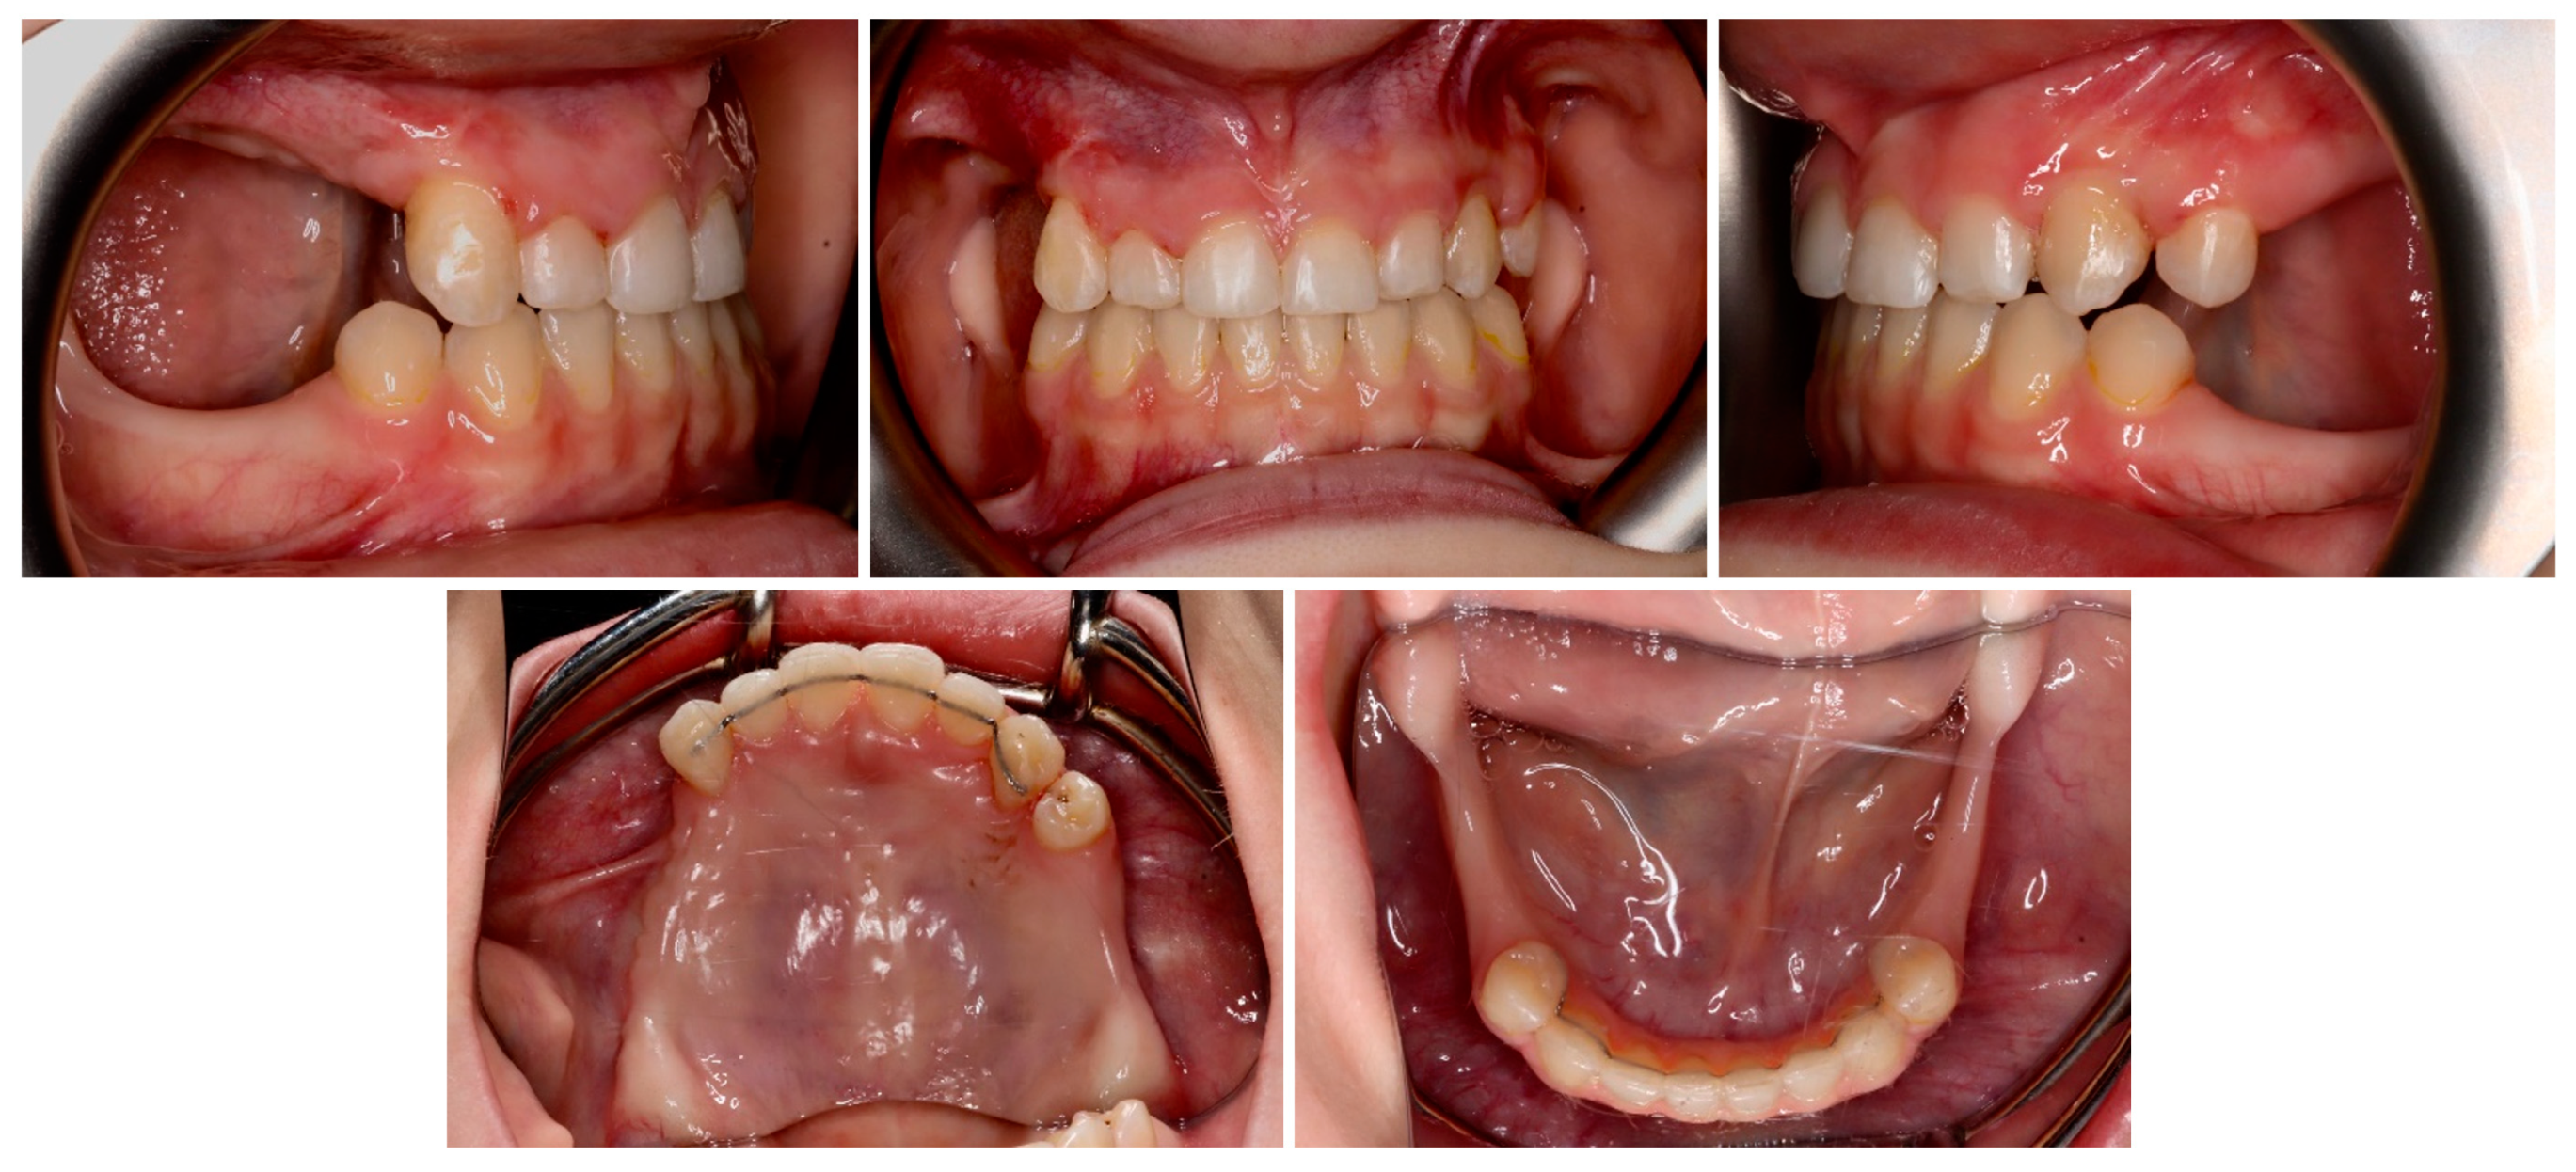

| May–August 2022 | Finishing; control panoramic X-ray (Figure 8); 1st canine relationships and midline consistency; debonding of the brackets; fixed upper and lower retainers’ placement (0.027″ × 0.011″ 8-strand braided SS), tooth no. 24 was not fixed to the retainer due to increased mobility. |

| September 2022 | E-max (lithium desilicated ceramic) veneers on upper teeth; individual implant abutments (titanium pre-milled abutments) and implant-supported blocked crowns (zirconia veneered with porcelain using the cut-back technique) on dental implants; removable thermoformable retainer. |

| March 2023 | Retention phase: 10-month follow-up. Stability of treatment results; minimal opening of the spaces mesially to teeth no. 34 and 44; proper mobility of tooth no. 24. Bleaching of the lower teeth. |